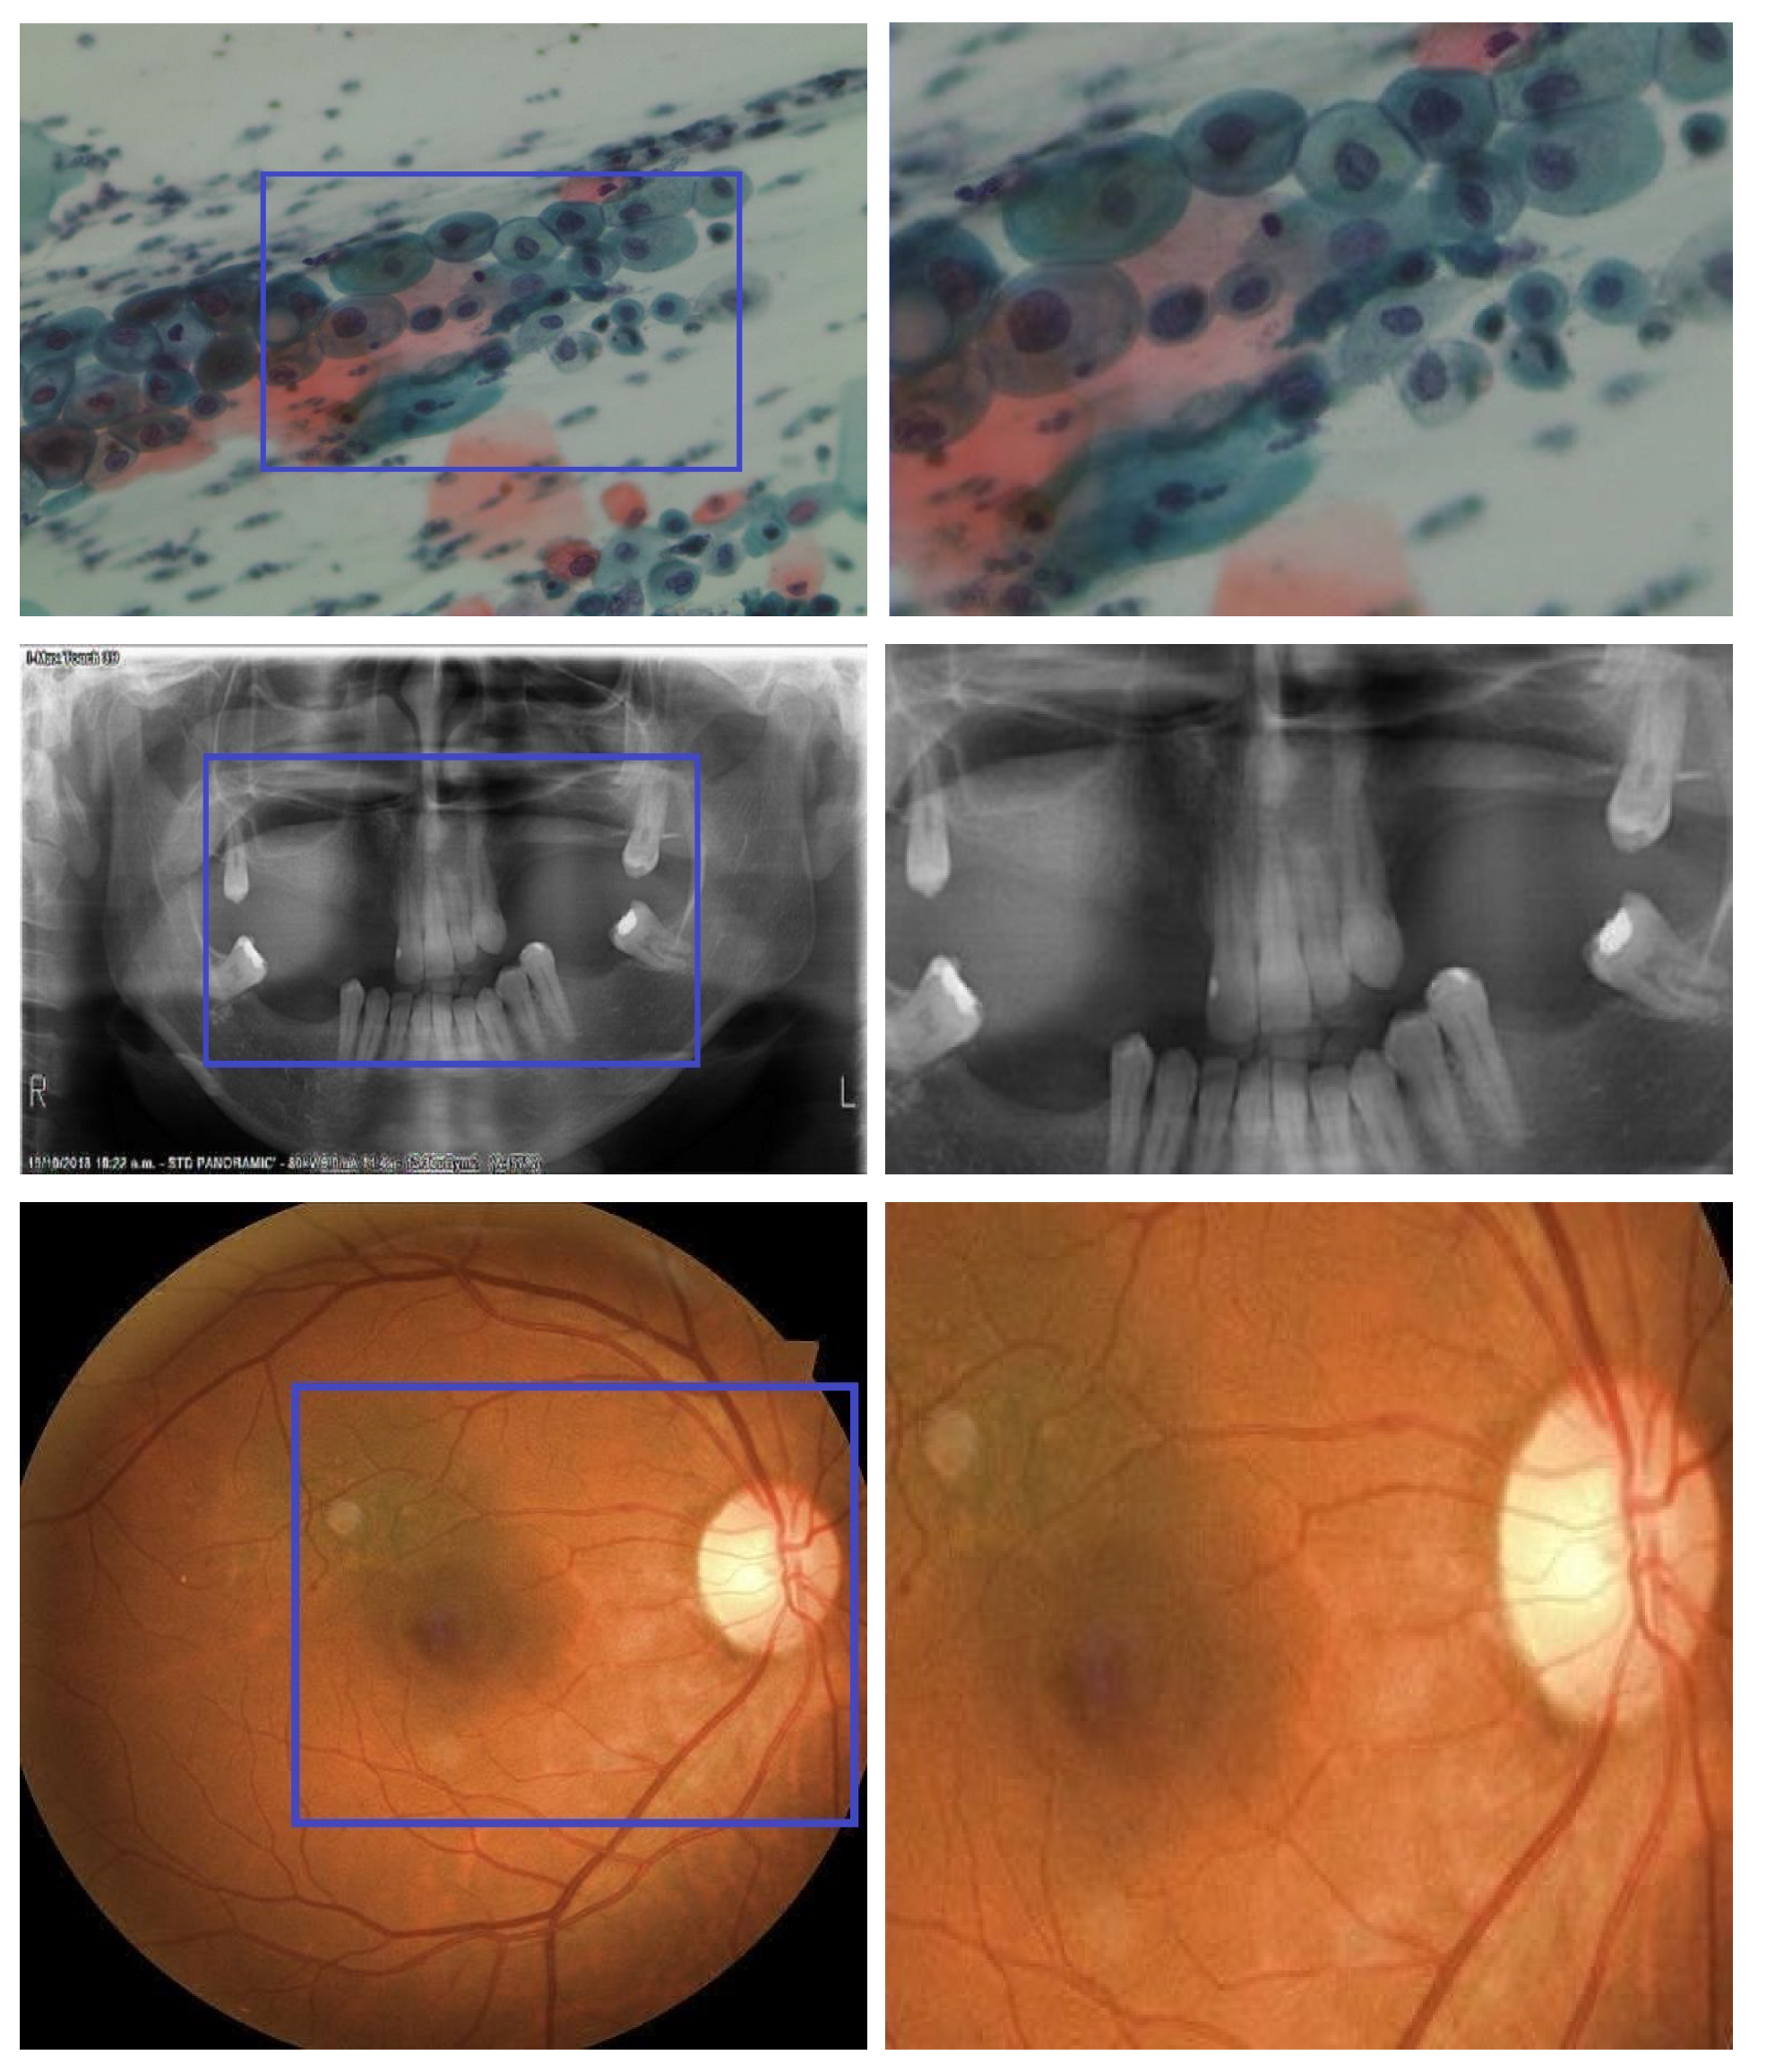

4.3. Subjective Evaluation